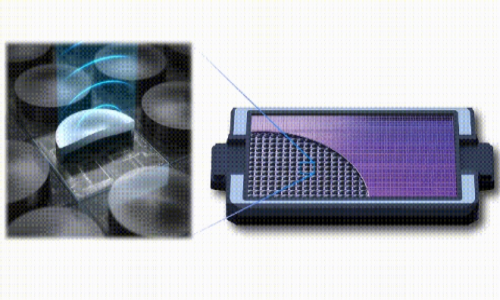

由 Butterfly 开发的超声波硬件将大型临床超声系统的音频生成、控制和记录功能集成到一个芯片大小的设备上。Forest 计划基于这些超声波芯片,利用定向的集中超声波来刺激大脑,并使用 fUSI 测量神经活动。

Butterfly Network 的超声波芯片示意图,源自http://www.youtube.com/watch?v=B1g-qvH9RgY